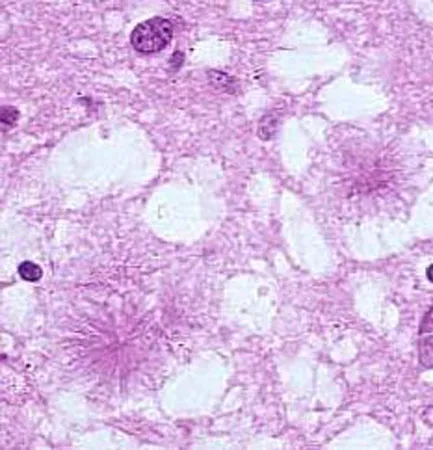

Virus vCJD bắt nguồn từ thịt bò bẩn….Loại virus này có thể gây chết người.

Giáo sư John Collinge, Chủ tịch Hội đồng nghiên cứu về các bệnh truyền nhiễm của Anh cho biết, thành công này sẽ cho phép các nhà nghiên xác định sớm và chính xác người có mầm bệnh, qua đó bệnh nhân được điều trị kịp thời, trước khi vCJD gây ảnh hưởng tới não.